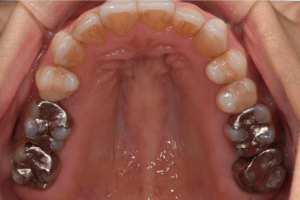

治療前:上の歯

担当医師所見:

臼歯部に残根状態の歯牙があり、またカリエス(虫歯)の散在が認められる。残根部分の両隣在歯は欠損部に対して傾斜し始めている。

治療後:上の歯

左上第1大臼歯は抜歯し、仮歯に置き換えた後治癒を待ちジルコニアBrで補綴。また右上第1大臼歯は根管治療終了後にジルコニアクラウンで補綴。前歯部は審美性を考慮しジルコニアボンドにて補綴した。 色調、形態共に調和がとれている。